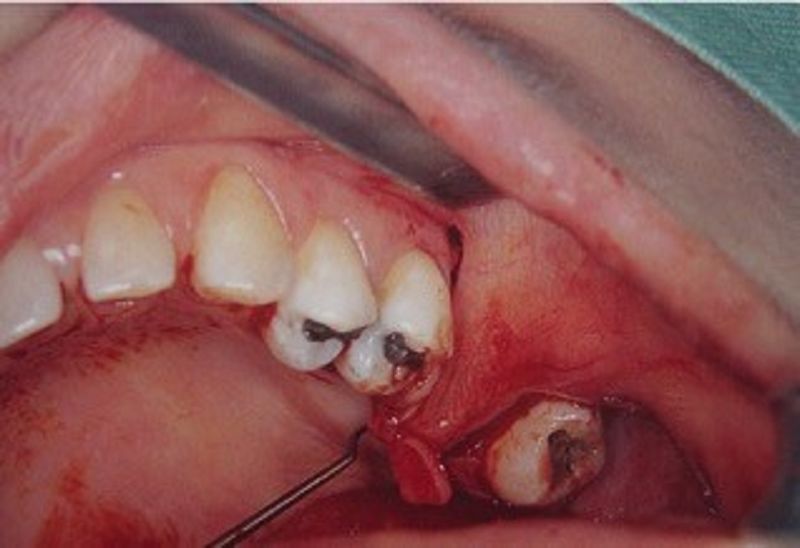

45. What is it called?

Hematoma

Infection

Liver clot

There are corrects